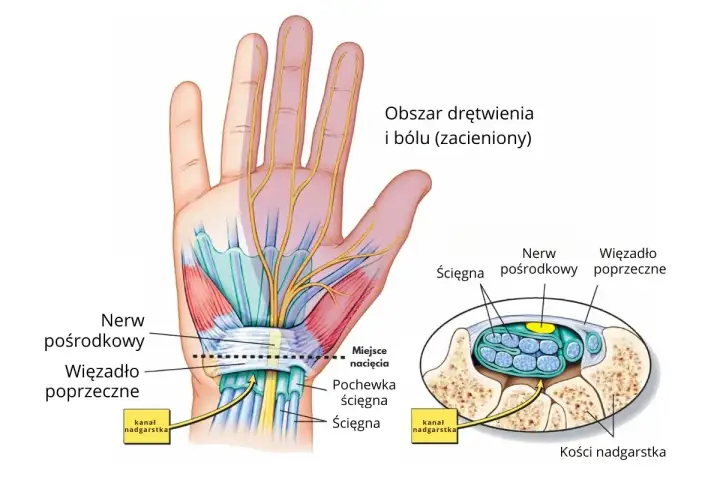

Anatomia nadgarstka - Klucz do zrozumienia bólu i rehabilitacji

Ból nadgarstka? Poznaj jego złożoną budowę, ruch i najczęstsze przeciążenia. Odkryj, jak anatomia wpływa na rehabilitację. Sprawdź nasz przewodnik!